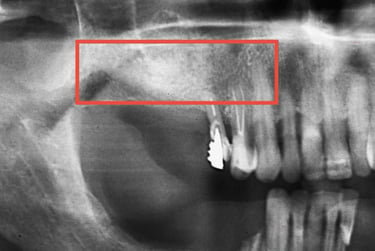

O planejamento da cirurgia dos dentes do siso normalmente é realizado por meio de tomografias computadorizadas. Elas permitem visualizar com precisão a localização do canal mandibular (seta), cuja lesão durante a cirurgia pode causar complicações neurossensoriais e hemorragias, reforçando a importância de um bom planejamento cirúrgico.